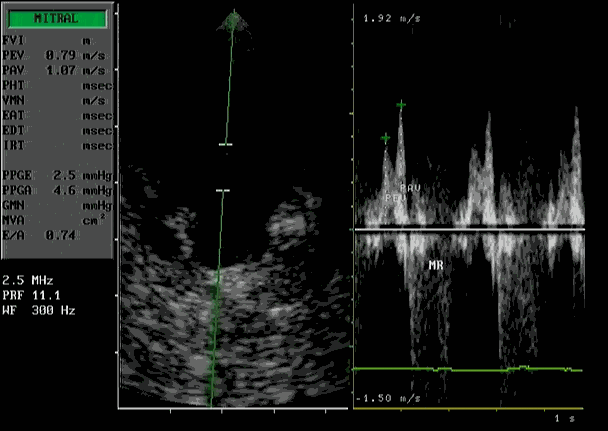

De diagnose kan alleen gesteld worden met een echocardiogram gecombineerd met kleuren Doppler.

Dit onderzoek zegt niet alleen iets over de beweging en grootte van de diverse hart-structuren, maar ook iets over het functioneren van het hart. De wanden van het normale hart zijn normaal 0,55-06 cm. Bij HCM is dit vaak meer dan 0,9 cm.

| Verdikte wanden linker kamer | Flowmeting met Doppler |

Doppler bij HCM:

Hierbij wordt het flow patroon door de mitraalklep zichtbaar gemaakt bij verminderde contractie van de hartspier. De pieksnelheid tijdens de vullingsfase is verminderd, de snelheid na de contractie van de linker boezem is toegenomen.